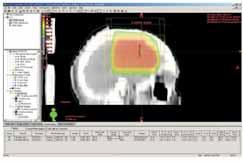

Obr. 1a Ozařovací technika 2 kolmých polí na

oblast lůžka tumoru a okolního edému s lemem: rozložení izodóz v

transverzálním CT řezu v rovině isocentrac

Obr. 1b Boost na lůžko tumoru, ozařovací

technika 2 kolmých polí: rozložení izodóz v transverzálním CT řezu

v rovině isocentra.

Podle lokalizace PTV a při ozařování celého mozku byla volena

technika 2 protilehlých polí (laterolaterálních), při lokálním

ozáření (obr.1a,2a,3a) a při boostu (obr.1b,2b,3b) byla většinou

volena technika 2 kolmých polí. Vždy šlo o isocentrické techniky.